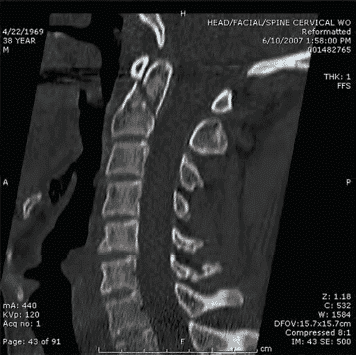

Близько 10% пацієнтів з переломом шийного відділу хребта мають інший, несуміжний, перелом хребта. Цей факт є підставою для повного рентгенологічного дослідження всього хребта в пацієнтів з переломом у шийному відділі.

За наявності неврологічної недостатності рекомендоване проведення МРТ-дослідження для визначення компресивного ураження м’яких тканин, яке неможливо виявити на рентгені або МСКТ: наприклад, епідуральної гематоми спинного мозку або ж травматичної грижі міжхребцевого диску. МРТ-дослідження також може показати забій чи розрив спинного мозку, а також ушкодження навколохребтових зв‘язок і м’яких тканин. Однак, МРТ-дослідження часто неможливо провести для пацієнтів з гемодинамічною нестабільністю. У такому разі згадані специфічні дослідження слід проводити на розсуд нейрохірурга.